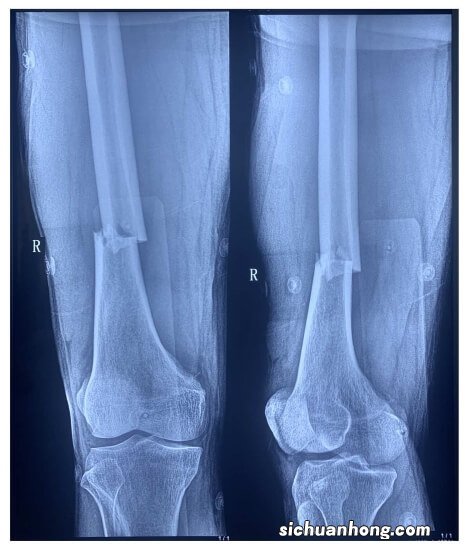

图2e 。营养性佝偻病–3岁女孩,因家长疏忽造成股骨骨折 。(e)两年后随访可以看到 , 两个下肢的弥漫性骨质减少,胫骨和腓骨的弯曲 , 干骺端的扩大 。干骺端可见平行于骨骺生长板的线样骨质密度增高(箭头)影,即生长障碍线,反应了骨化的周期性变化 。(图片由Ok-Hwa Kim , MD,Ajou大学提供 。)